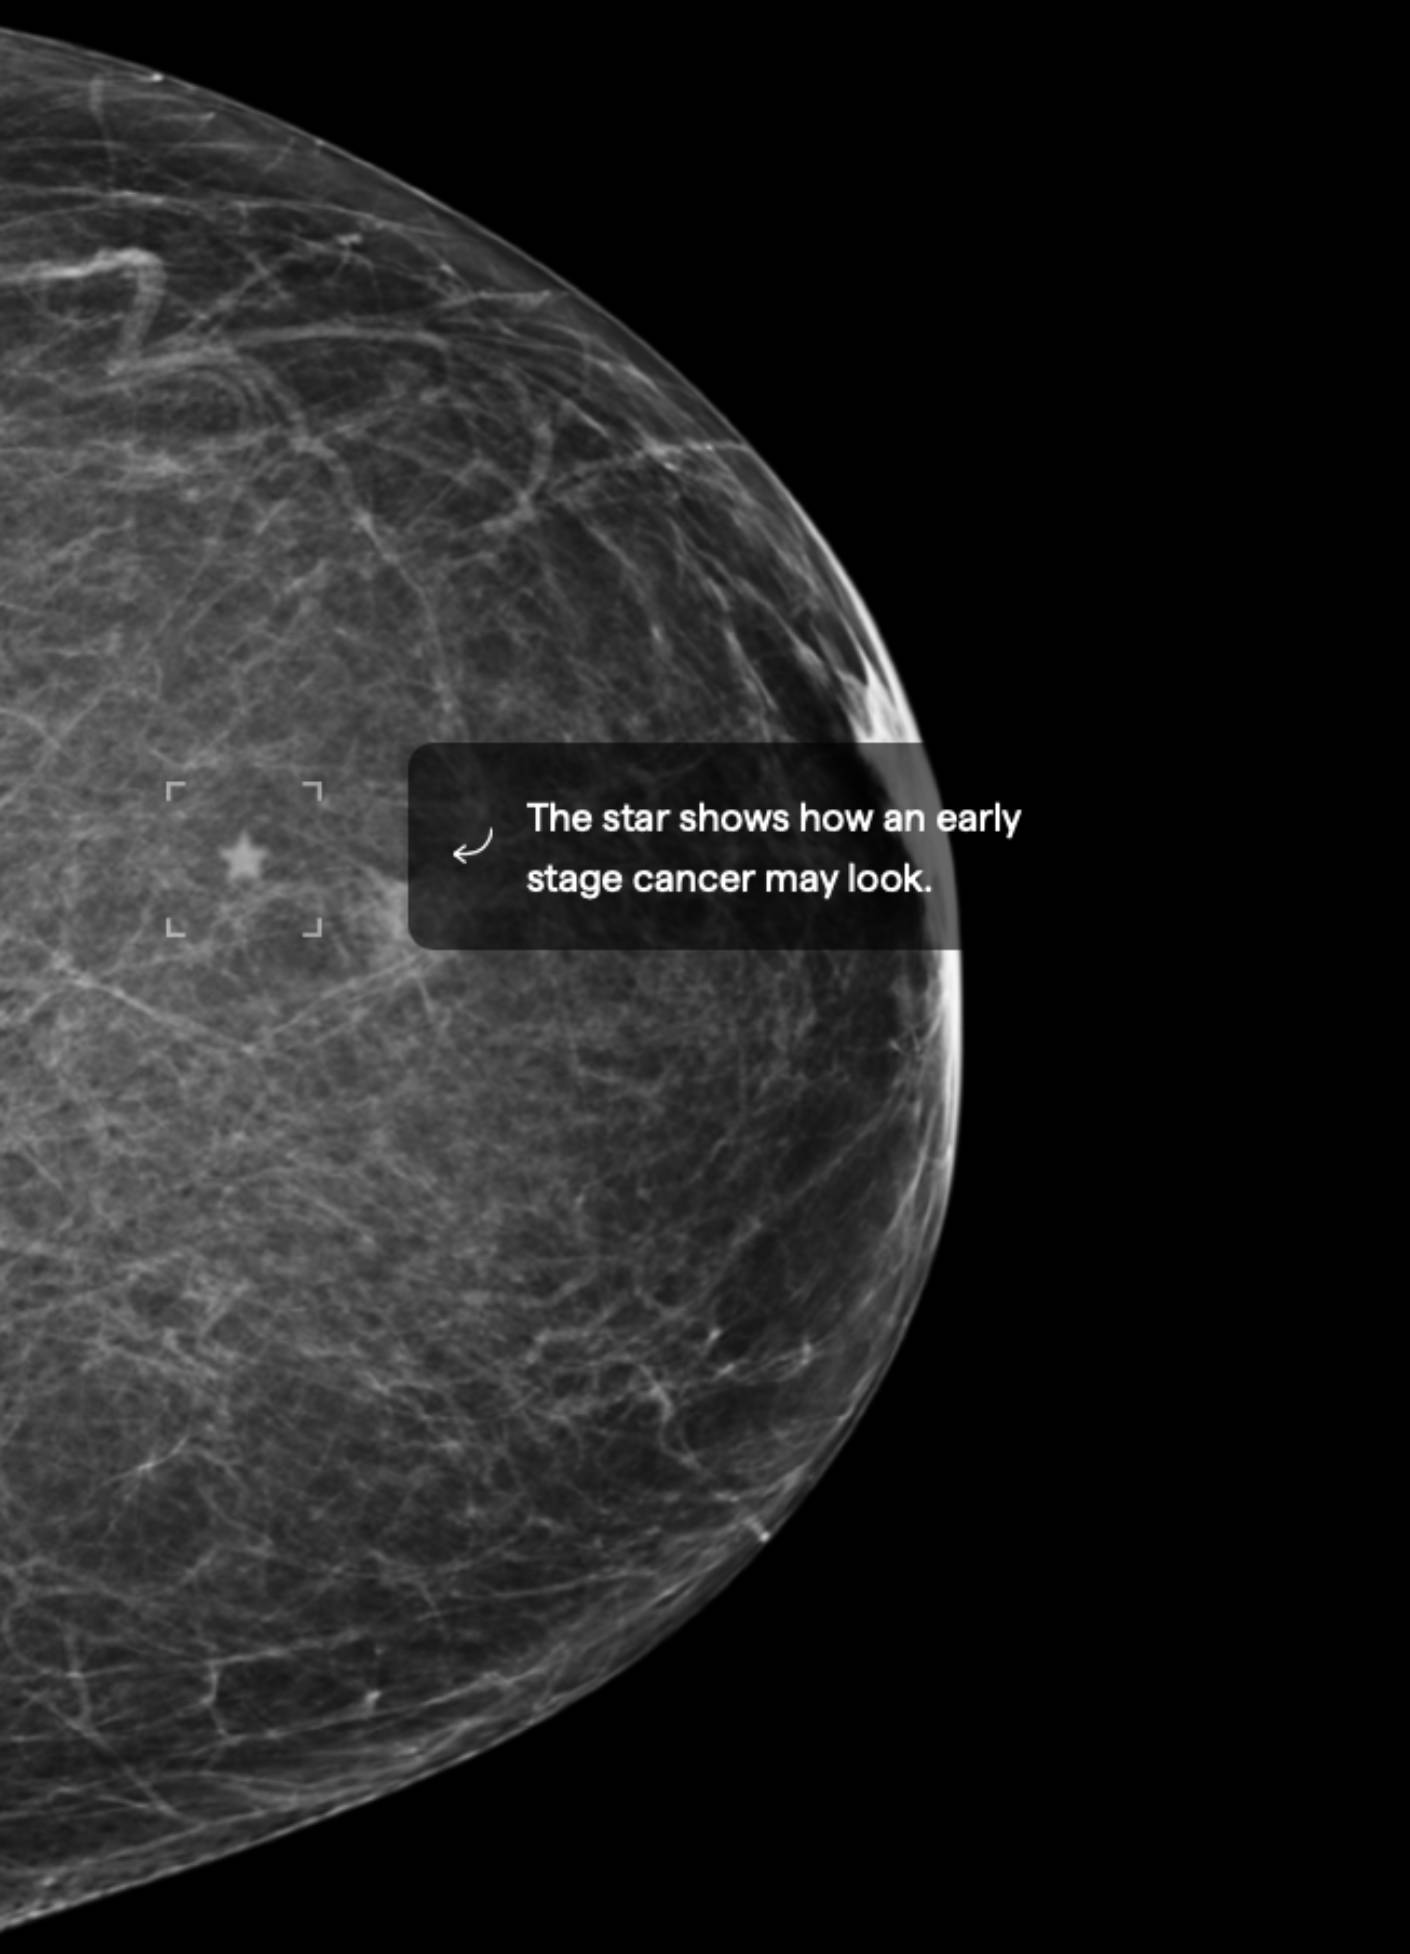

3.5% Mammographic Density

About 40% of female breasts fit category “B”. They are referred to as breasts with “scattered areas of fibroglandular density”.1

If you are over the age of 40 and in good health, an annual mammogram is recommended.2 Also consider asking your doctor about a risk assessment to help both of you better understand your lifetime risk for breast cancer.